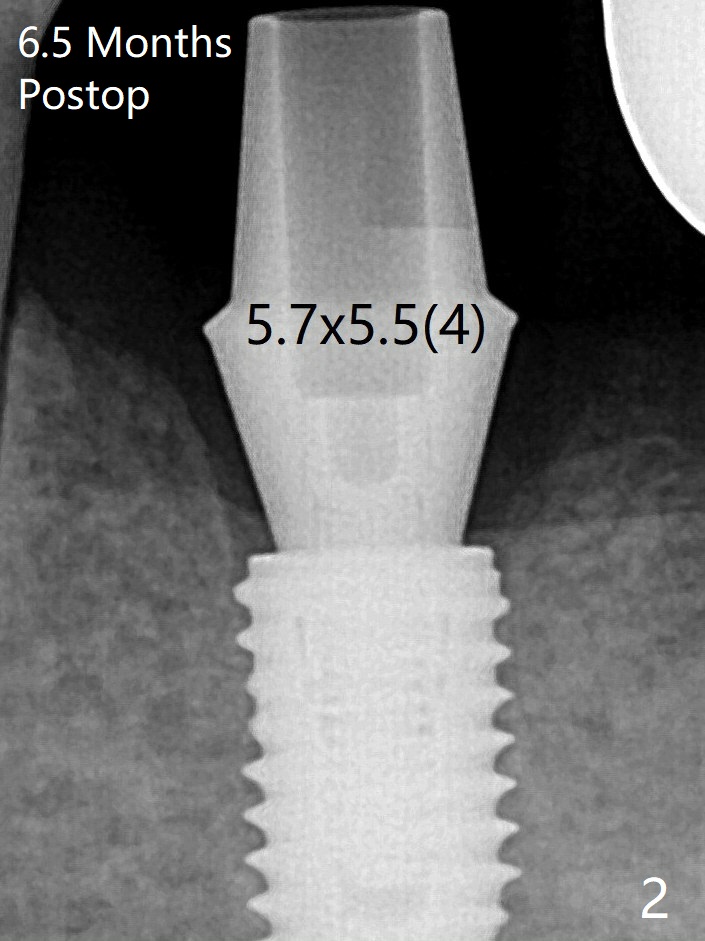

虽然愈合基台似乎完全就位,但是接近近中,远中牙槽嵴(图一:*),去除后,使用6毫米profile钻头,再次放置。术后病人没有任何不适。术后6.5月,基台完全就位,与没有牙槽嵴阻挡有关(图二)。骨质密度高,植入扭力高,没有造成骨质吸收。